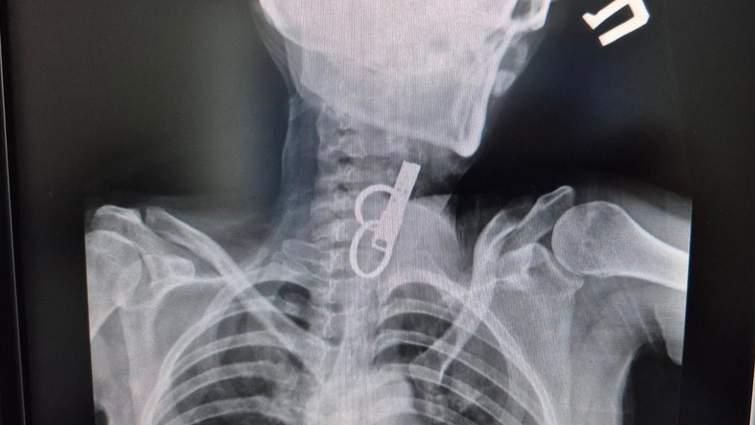

«Це дуже показовий випадок, що нам вдалося її врятувати. Як свідчить практика, переважно такі хворі гинуть. Спочатку ми не могли зрозуміти, що застрягло у стравоході. Це були якісь металеві кільця, які стояли зверху, а далі було ще якесь чужорідне тіло. Я здогадався, що це може бути ключ від дверей і почав його обережно витягувати», – розповів Олександр Садовий.

З’ясувалося, що ключ жінка проковтнула, щоб не віддати його родичам і, щоб вони не мали доступ до її помешкання. Лікар додає, що в обласну лікарню у Тернополі не ризикнули везти пацієнтку, оскільки її вже доставили в стані шоку, то жінку просто б не довезли. Рішення про операцію приймали за лічені хвилини.